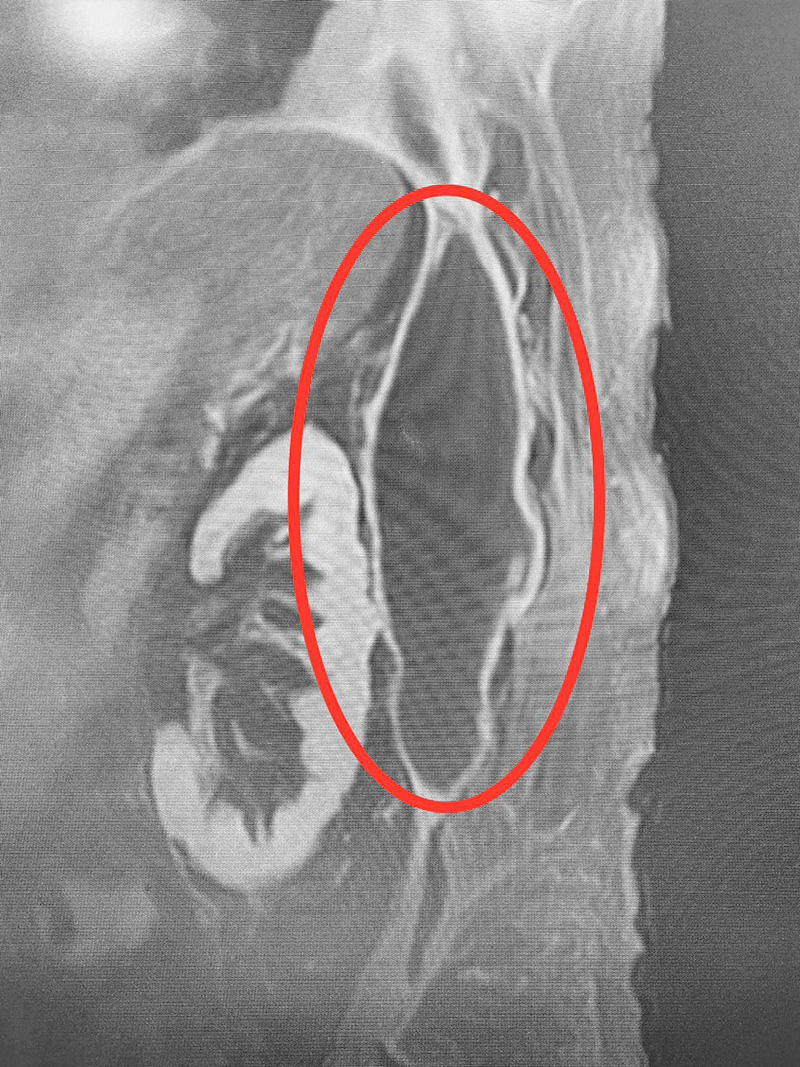

โดยระบุว่า "ปวดหลังที่ไม่ใช่ปวดหลัง อีกแล้ว !!! วันก่อนเจอคนไข้ปวดหลังเรื้อรัง สุดท้ายเป็นมะเร็งก้อนใหญ่ยักษ์ คนนี้ก็ปวดหลัง ตรวจ MRI กระดูกสันหลัง พบหนองรอบไต ดูดออกมายังกับ matcha green tea !!! ปวดหลัง...เรื่องเล็ก ๆ แต่บางทีไม่เล็กนะ"